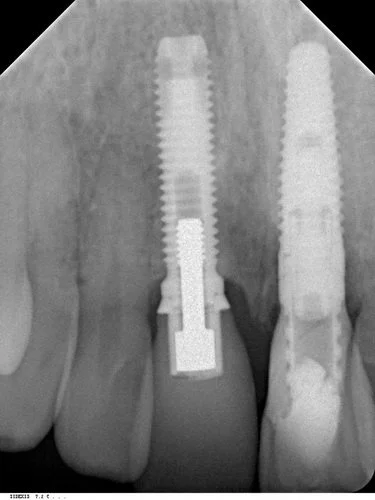

Tooth 21 was removed and due to excellent primary stability being achievable, with good interproximal bone height (Tarnow 1998) a Replace Select implant was placed immediately, with 40+ Ncm of torque being achieved. This allowed for placement of an immediate provisional restoration. The patient’s natural crown was used along with a titanium provisional abutment to construct a pleasing provisional restoration.

The abutment screw was torqued finger tight (~15 Ncm). The access cavity was then restored with cotton pellet and Cavit. The occlusion was adjusted to give no shim stock hold in ICP and no guidance in protrusion or lateral excursion.